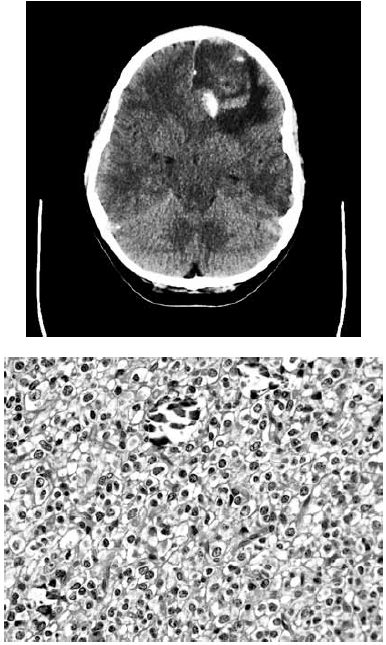

Paciente de 30 anos com quadro de cefaleia há alguns meses e história de primeira crise convulsiva há 1 semana. Não apresenta deficits neurológicos.

Apresenta esta imagem de tomografia computadorizada sem contraste e, após a cirurgia, observa-se tal lâmina em cortes HE.

Qual a sua impressão diagnóstica: